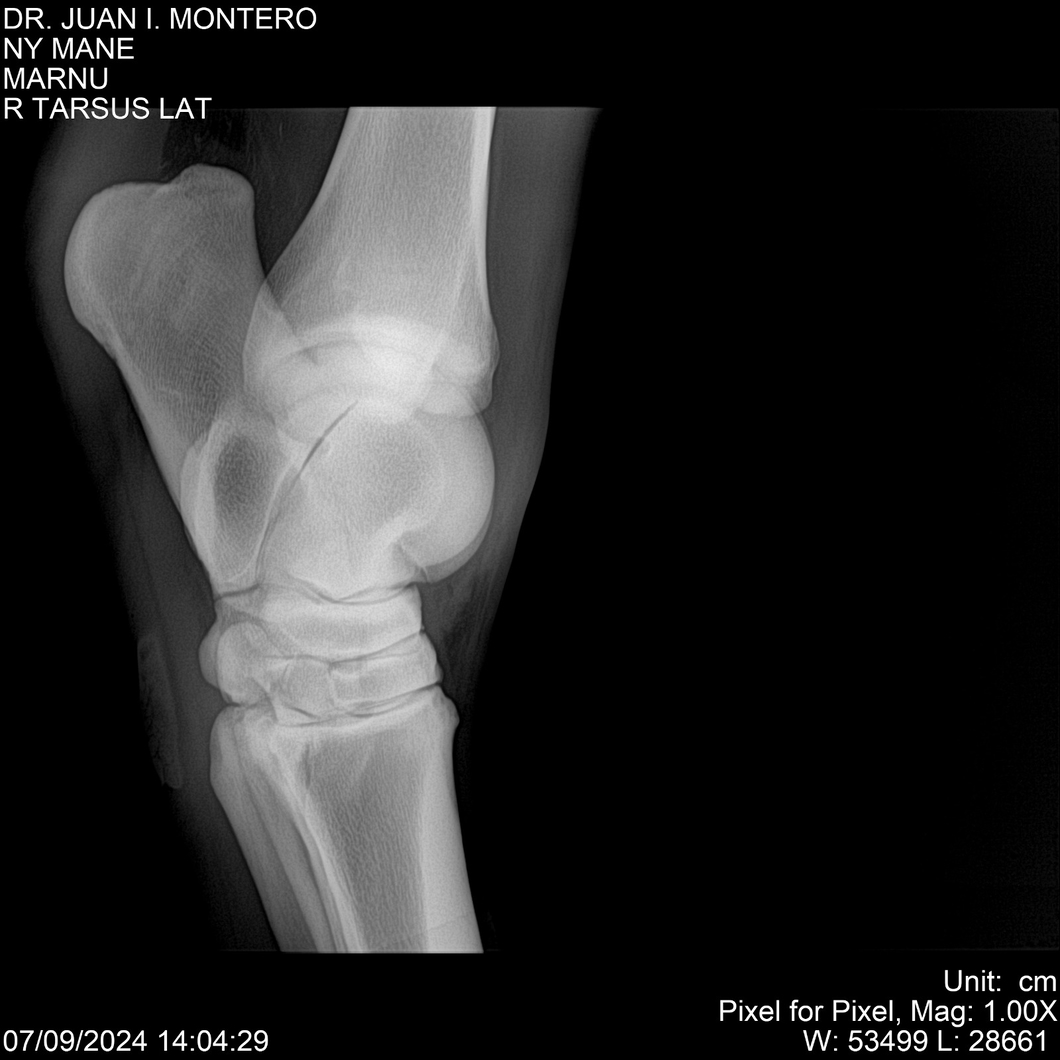

LOTE 20, NY MANE Lote Anterior Volver al remate Lote Siguiente Ficha Contacto Montevideo - Ficha del Lote Identificador: #282520 Categoría: Yeguarizos 76 Visualizaciones ClicData Contacto Empresa: Abelenda N. R., Walter Hugo Nombre*: Teléfono* : E-mail* : Mensaje Enviar Registrese gratis Este contenido Exclusivo está disponible sólo para usuarios registrados Ingresar